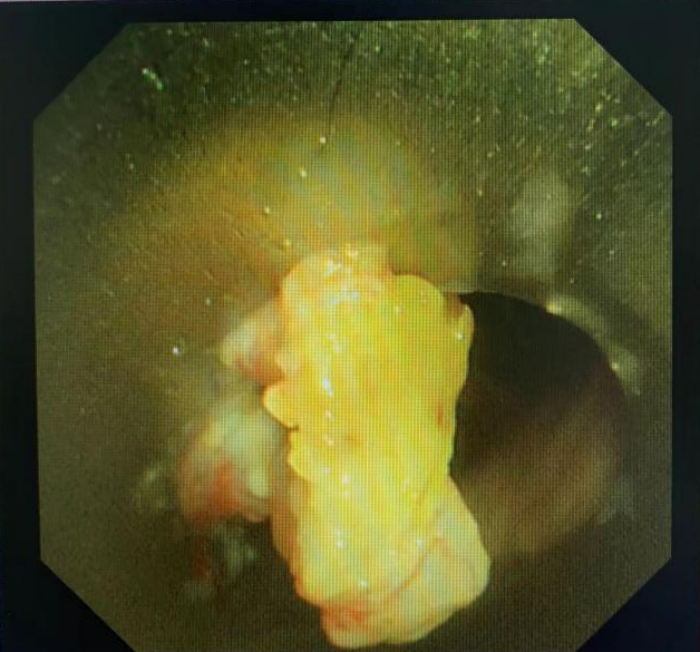

患者为一名老年男性,因肺鳞癌行左肺切除术以及右主支气管小Y型金属覆膜支架置入术后,近期患者因活动后胸闷气促,再次入我科行进一步治疗。支气管镜检查提示:主气管新生物堵塞管腔,根据患者的病情,经肖祖克主任医师、吴西雅、梁莹及介入团队充分讨论评估后,决定为其实施全麻下“经硬质支气管镜单导丝引导下气道Y型覆膜支架置入术”。

术前主气管下段肿瘤组织突入管腔